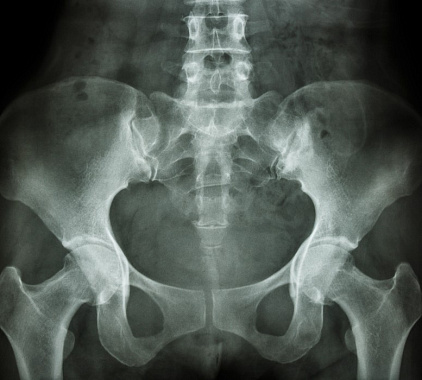

Рентген таза в норме:

- Положение лонных костей без изменений. Их нижние и верхние ветви лишены смещений.

- Головка бедренной кости соответствует размеру и форме вертлужной впадины.

- Межкостные хрящи соответствуют нормальным значениям. Размер суставной щели в норме.

- Околосуставные мягкие ткани без изменений.

- Опухоли, остеопороз, травмы и их последствия не визуализируются.